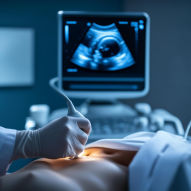

3. 합병증별 위험 증상 비교표 (즉시 병원 방문)

방치된 고지혈증이 혈관을 막아 질병이 되었을 때 나타나는 증상들입니다. 이 증상이 있다면 응급 상황일 수 있습니다.

| 뇌졸중 (중풍) | 한쪽 팔다리 마비, 말 어눌함, 심한 두통 |

뇌혈관 막힘 또는 터짐 |